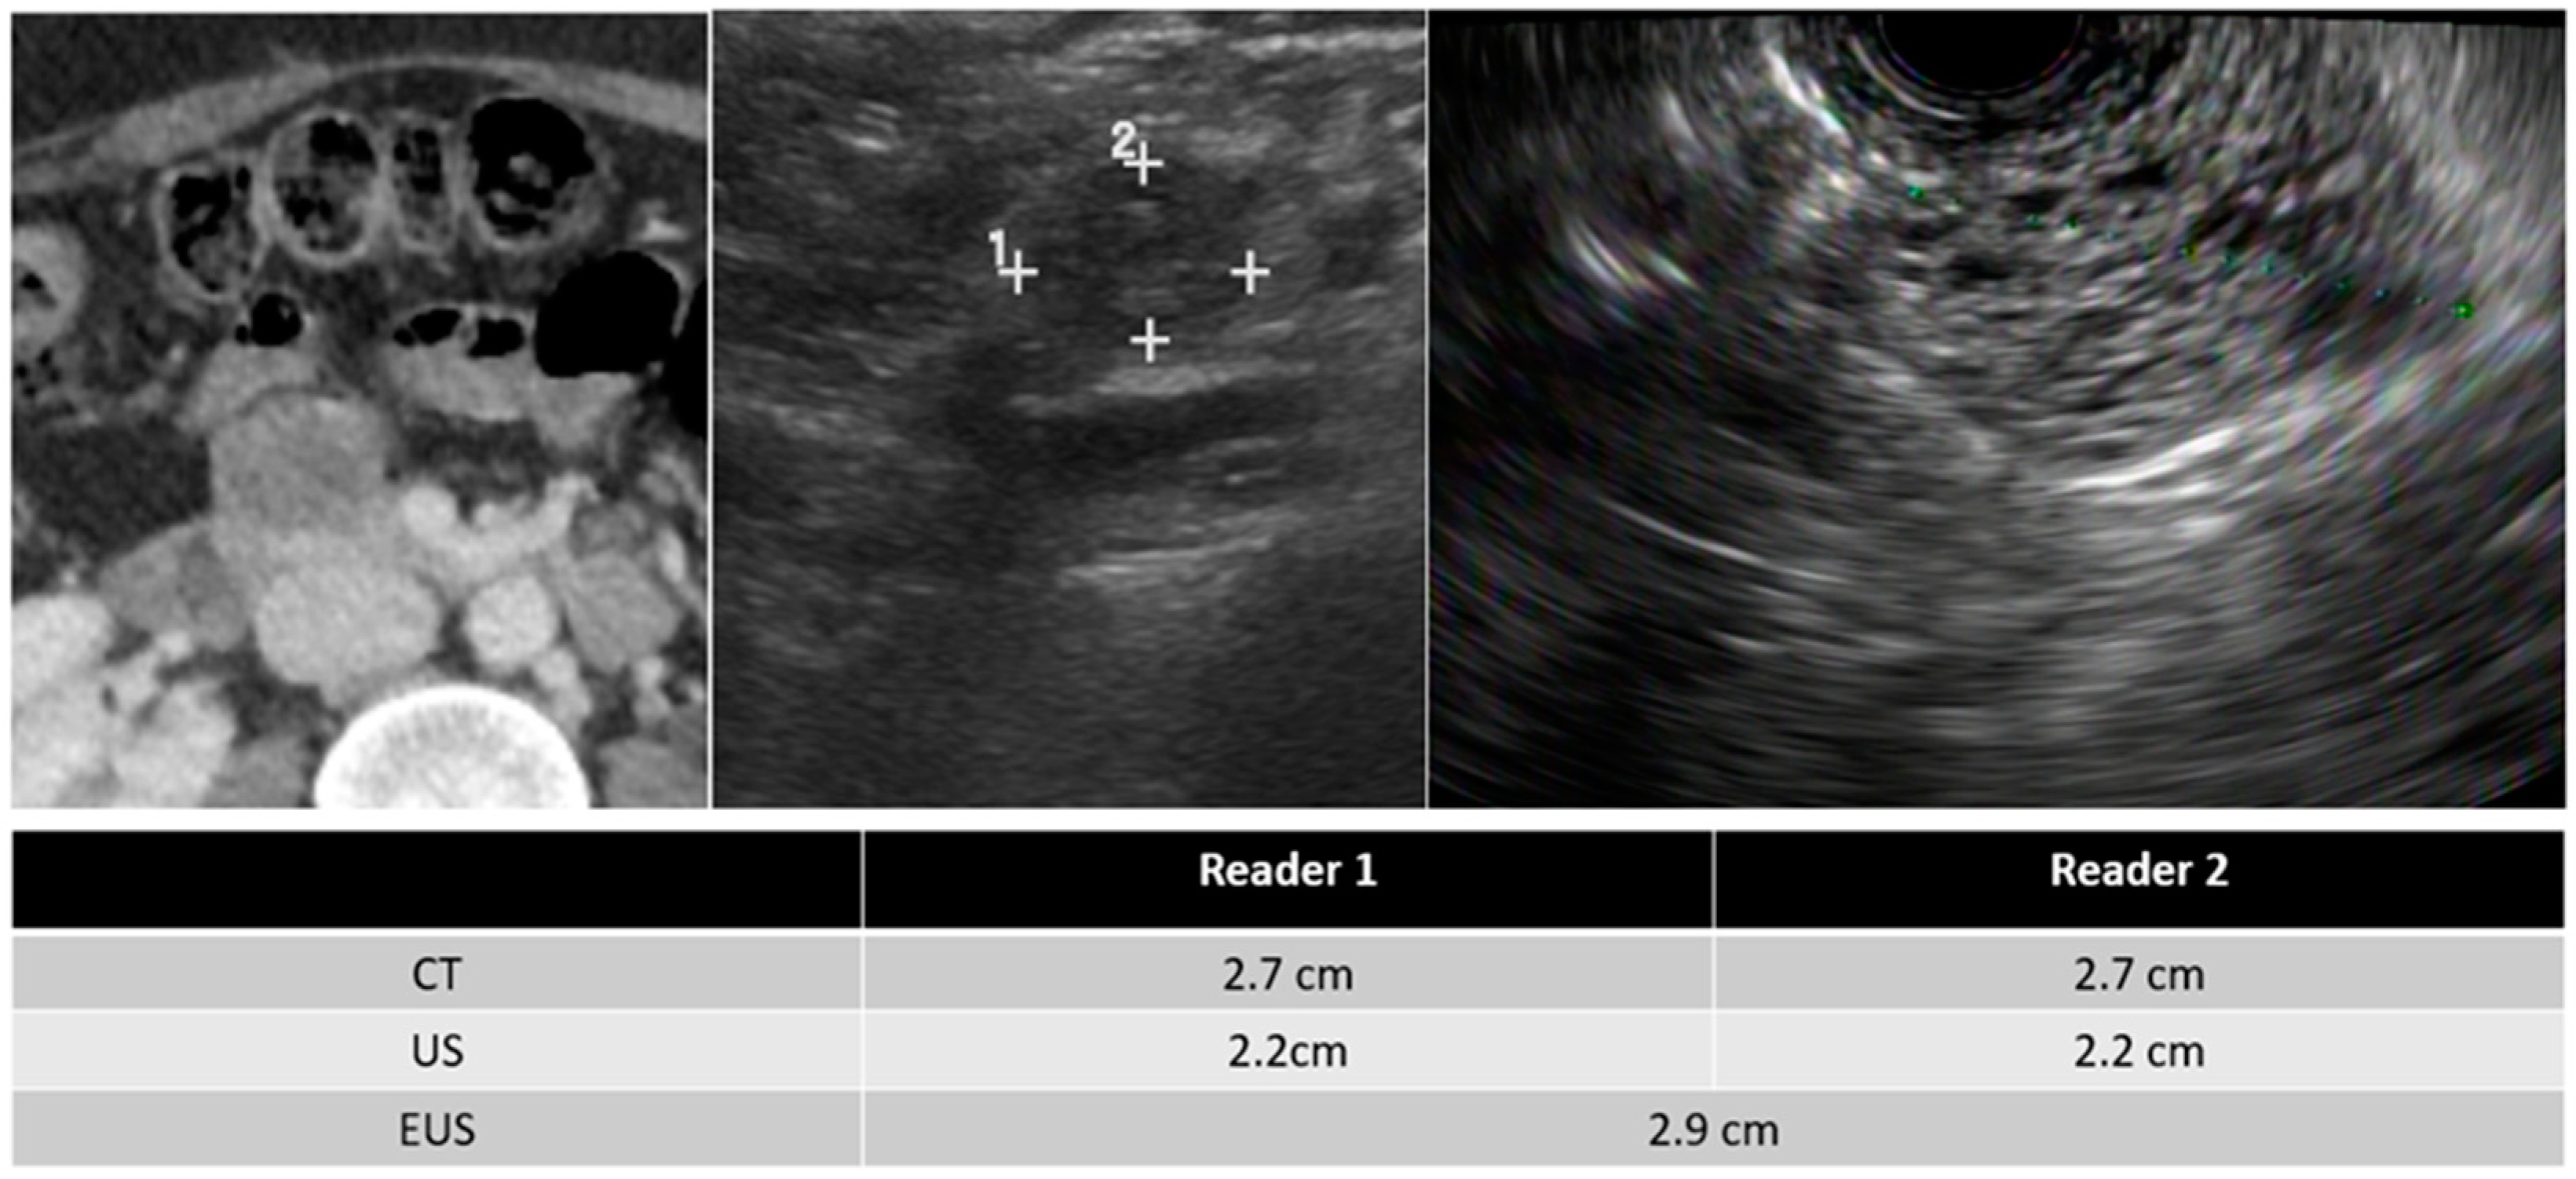

| Mean size of detected PCLs (cm) | ||

| TAUS | 2.40 ± 2.65 | 2.41 ± 2.56 |

| CT | 2.45 ± 2.43 | 2.48 ± 2.53 |

| EUS * | 2.73 ± 2.10 | |